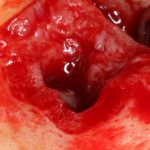

В общем, так и получилось. Уж не помню, почему я наобещал пациентке, что мы поставим ей имплантаты одновременно с остеопластикой. Но я наобещал. И, когда увидел клиническую картину в полости рта:

у меня появились серьезные сомнения, смогу ли я выполнить своё обещание. Вот только не спрашивай меня «Вот чо, сложно было по КЛКТ посмотреть?». Я же не спрашиваю тебя, где ты был в 2013 году, и сделал ли ты домашку. Но, в целом, план операции у нас не поменялся. Как и было оговорено, мы проведем остеопластику с одновременной имплантацией в боковом участке нижней челюсти справа.